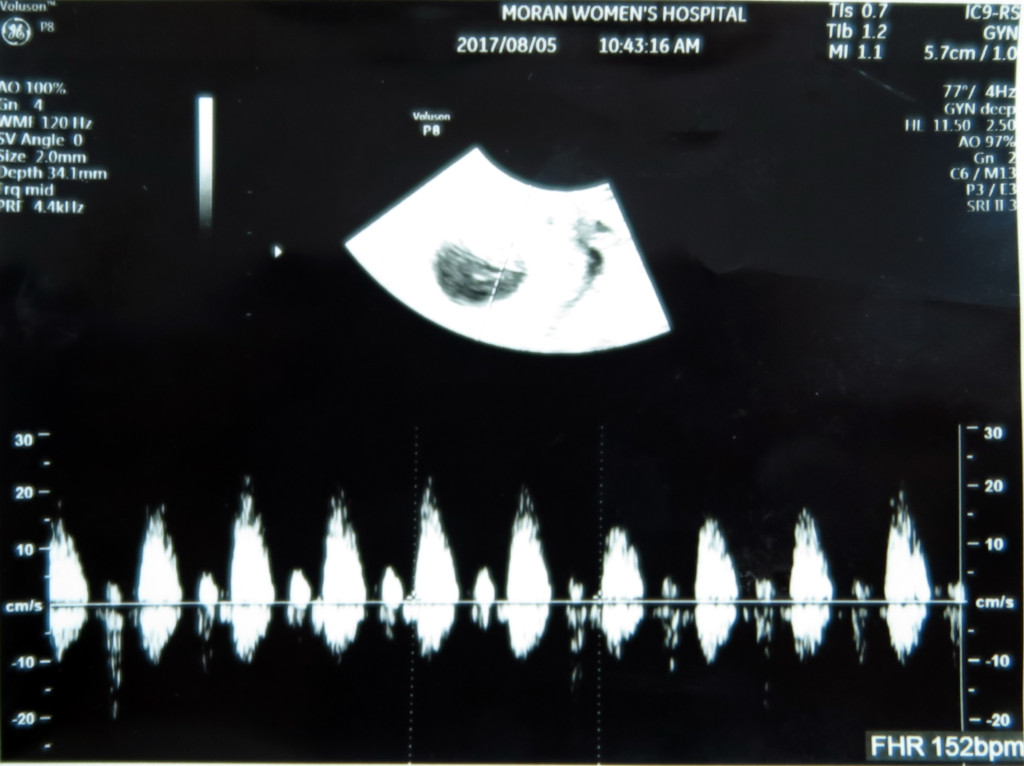

고 작은 녀석의 심장소리는 또 얼마나 우렁찬지.

서현이 때도 들었던 심장소리지만 또 들어도 마음이 울컥합니다.